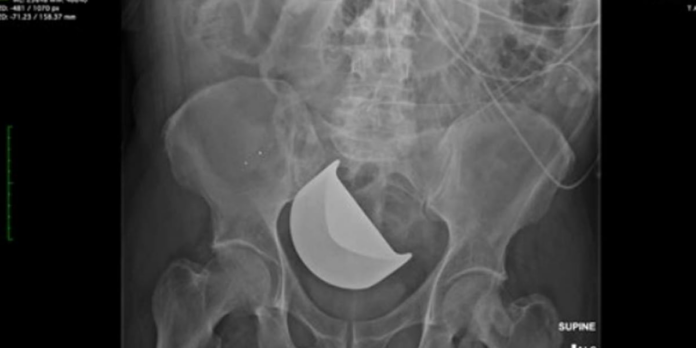

Documents state that at some point in the surgery, a Thompson retractor blade fell into or was placed inside Fulcher’s abdominal cavity. Bostock failed to see or remove the retractor blade and closed his abdominal cavity with the blade still inside Fulcher’s body.

The retractor blade remained in Fulcher’s body, undiscovered, for five days, and caused increasingly severe pain and eventually perforated his colon.

The lawsuit states that at midnight leading into the next day, Fulcher’s oxygen saturation level dropped, and his abdomen was distended. An x-ray was ordered at 2:00 a.m., and a radiology report stated a “large volume pneumoperitoneum,” which is a medical emergency that requires immediate intervention.

The findings were discussed with Hewitt, and over two hours later at 4:42 a.m., she entered a note determining that another round of imaging was necessary to conclude that the blade was actually still inside of Fulcher’s body rather than sitting on top of his pelvis.